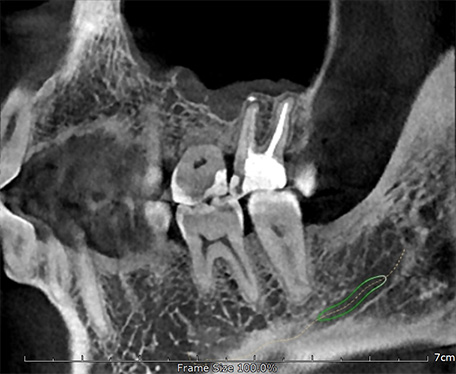

Высокотехнологичный детектор с самым высоким разрешением в классе – 70 мкм. Позволяет различить даже самые мелкие анатомические образования и облегчит постановку диагноза в сложных случаях. А вместе с применением алгоритма SMARF инородные тела из металла не испортят качество снимков.

Алгоритм уменьшения вторичного излучения от металлов

Умная Функция Уменьшения Артефактов от Металла (Smart Metal Artifact Reduction Function) – позволяет минимизировать артефакты от вторичного излучения металлов и получить необходимую диагностическую информацию для постановки корректного диагноза, а также планирования и контроля проведенного лечения.